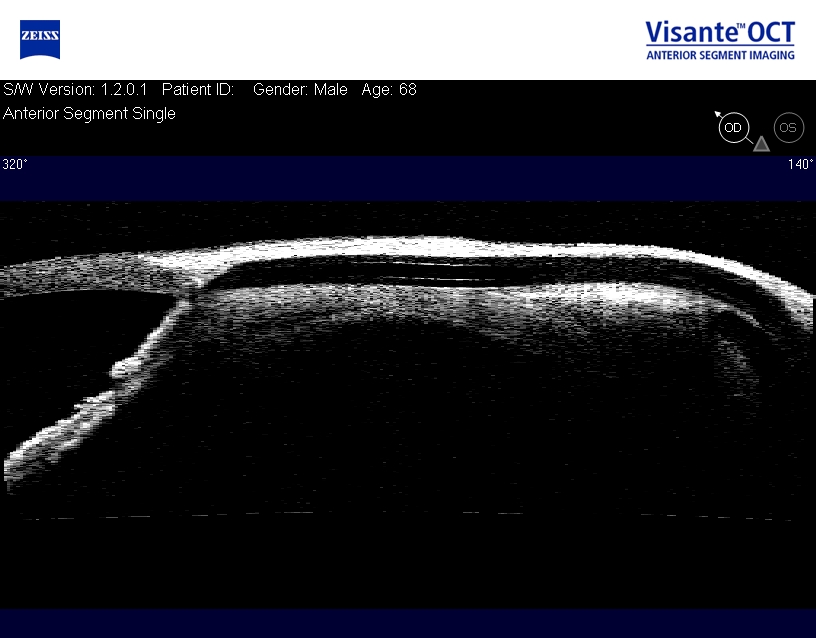

Оптическая когерентная томография переднего отрезка глаза вносит большой вклад в изучение причин гипертензии, визуализации путей оттока внутриглазной жидкости и оценки местоположения дренажей и дренажных устройств. Нами у пациента после имплантации клапана Ahmed установлена миграция трубки в слои склеры, что в последующем привело к повышению ВГД (рис. 3). В литературных источниках встречается описание миграции трубки клапана Ahmed, которая развивается в долговременной перспективе и является редким осложнением. По данным F. Topouzis и соавт., встречаемость данного осложнения составляет 1/31 [19], тогда как D. Budenz и соавт. сообщили о частоте 1/413 пациентов [20].

3. ОСТ томограмма трубки клапана Ahmed смещенного в слои склеры | |